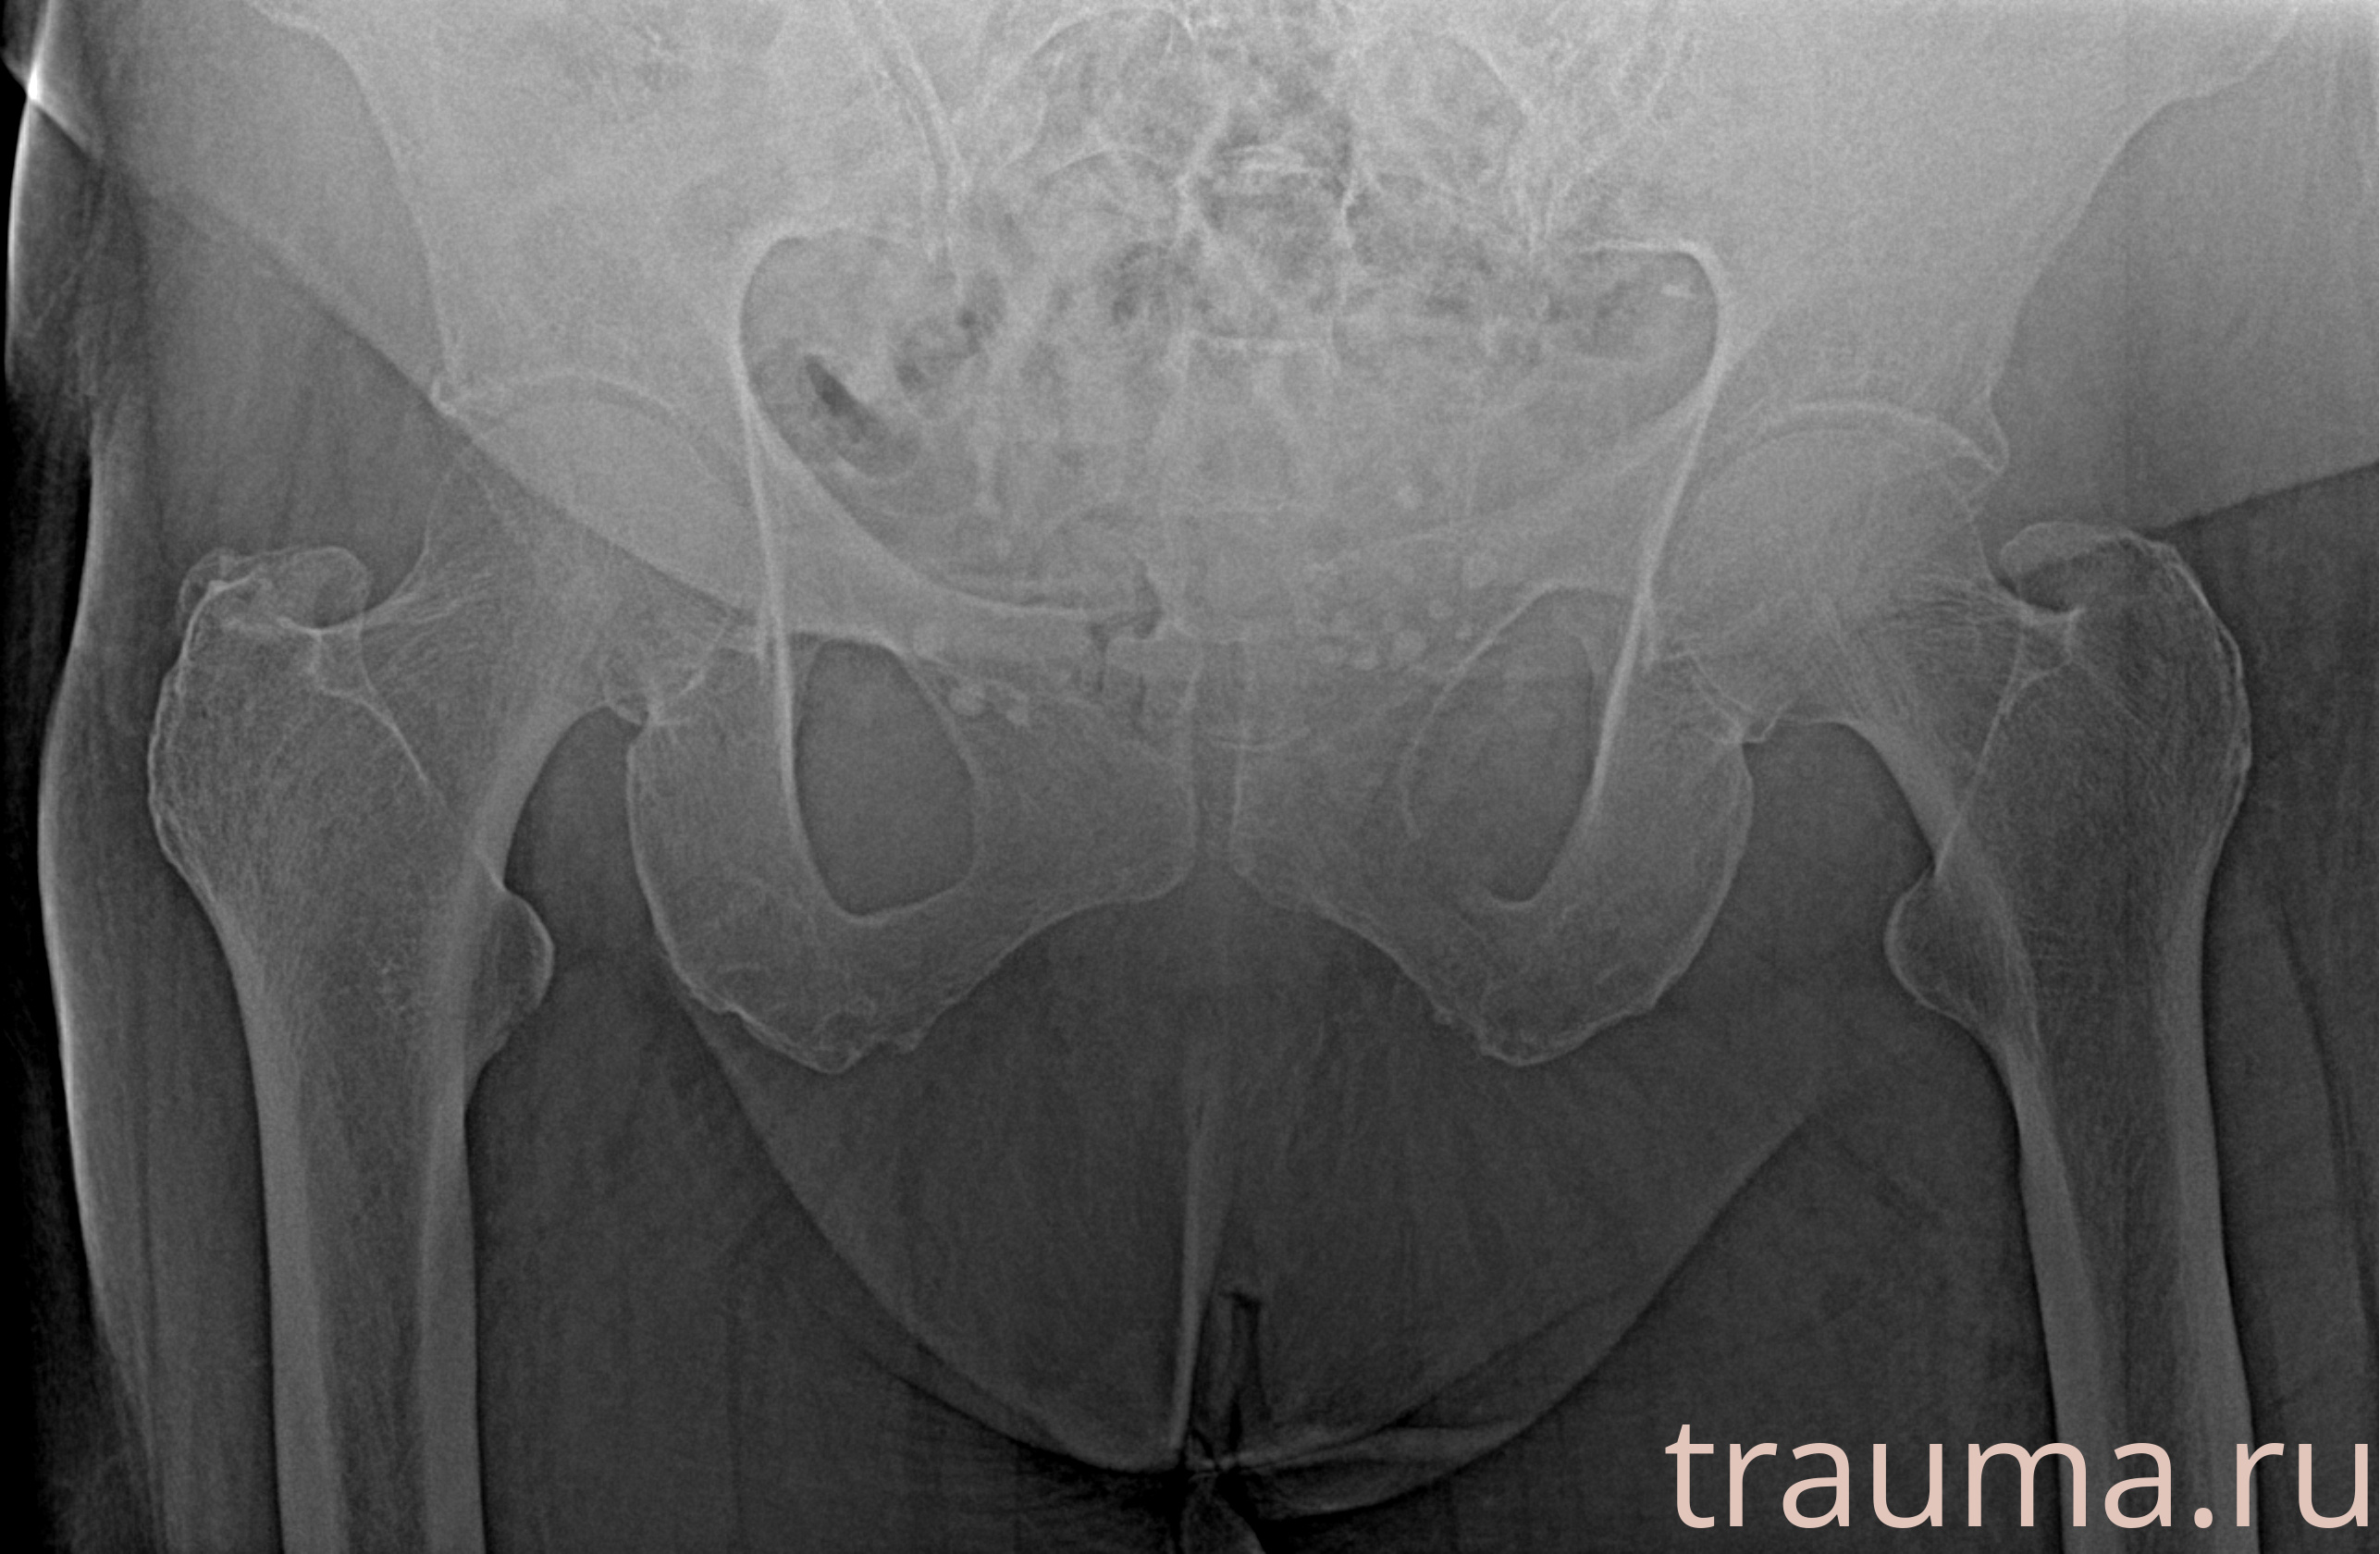

Рентгенограммы

Рентген на дому: по вашему адресу приезжает врач-рентгенолог, травматолог-ортопед с мобильным рентгеновским аппаратом, проводит диагностику травмы или заболевания, делает необходимые рентгенограммы, дает рекомендации по дальнейшему лечению. Получить качественные снимки в домашних условиях возможно благодаря уникальной методике, разработанной МосРентген Центром для института  Склифосовского